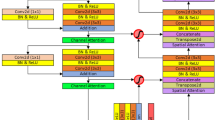

The method uses a cascade structure to improve the network’s extraction of information. First, the Side-output Feature Fusion Attention block is used to fuse features at different levels and combine with attention mechanism to focus on important information. Then, the Atrous Spatial Pyramid Pooling Attention block is used to extract multi-scale semantic features. Finally, the Multi-scale Prediction Fusion block is used to fully fused the features captured at each layer of the network.